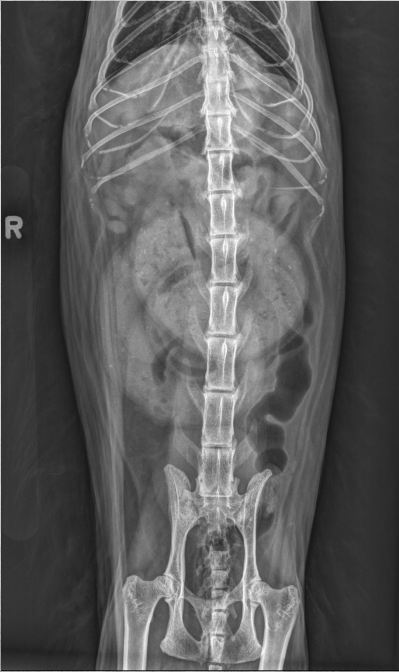

15 yo cat

Weight loss, anorexia, vomiting

Findings:

● Dilated bowel filled with fecal mass

– Not only large intestine, but small

intestine as well.

● Megacolon